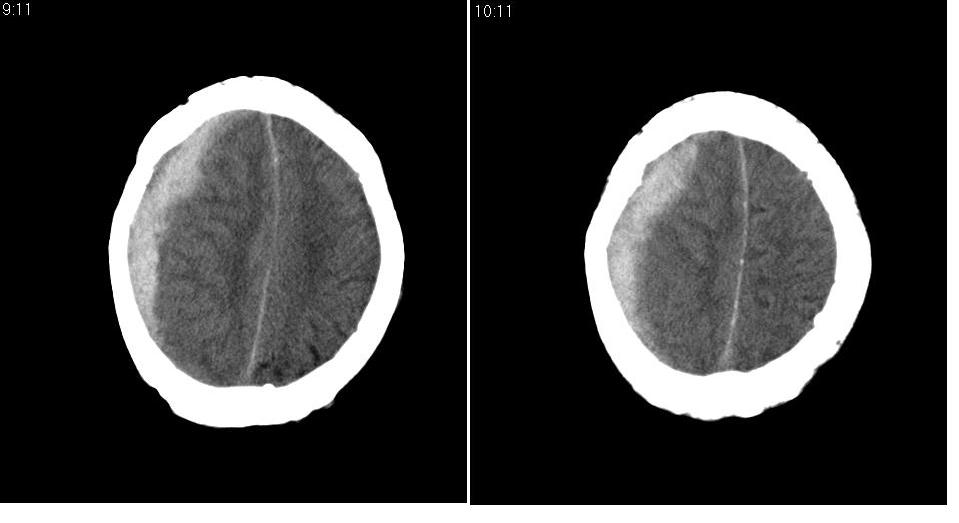

以下是引用川北影像在2007-8-14 15:33:00的发言:[br]1、右侧颞叶脑挫裂伤伴血肿形成。[br]2、右侧额颞顶部硬膜下血肿伴大脑廉下疝形成。

以下是引用gaoshengjiang在2007-8-14 16:30:00的发言:[br]大家都认为右侧颞叶脑挫裂伤伴血肿形成;右侧额颞顶部硬膜下血肿伴大脑廉下疝形成;蛛网膜下腔出血。 但硬膜下血肿、脑内血肿量不多,而大脑廉下疝明显,右侧颞叶类圆形高密度灶,周围轻度水肿,呈蟹足状,考虑脑内占位所致脑内血肿、突然晕倒、硬膜下血肿、颞叶脑挫裂伤等一系列改变。[br][br] [br]

以下是引用拾荒者在2007-8-14 21:59:00的发言:[br][quote]以下是引用gaoshengjiang在2007-8-14 16:30:00的发言:[br]大家都认为右侧颞叶脑挫裂伤伴血肿形成;右侧额颞顶部硬膜下血肿伴大脑廉下疝形成;蛛网膜下腔出血。 但硬膜下血肿、脑内血肿量不多,而大脑廉下疝明显,右侧颞叶类圆形高密度灶,周围轻度水肿,呈蟹足状,考虑脑内占位所致脑内血肿、突然晕倒、硬膜下血肿、颞叶脑挫裂伤等一系列改变。[br][br] [br]